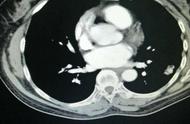

导致急性胸痛的原因很多,心血管方面,如:心肌梗塞、主动脉剥离;肺部方面,如:气胸、肺炎;肠胃系统方面,如:胃食道逆流;肌肉、骨骼、神经病变方面,如:肌筋膜炎、带状疱疹;精神疾患方面,如:恐慌症。

“生活中,有不少患者因持续咳嗽、咳血及胸痛等临床症状去医院就诊时,通过常规X线胸片或DR检查所发现的肿瘤多数已属中晚期。